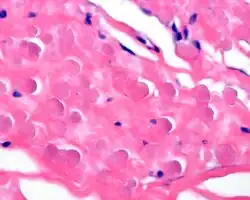

By microscopie view, there is an admixture of heavy dense bands of collagenous tissue dissected by fat and abnormal elastic fibers. The elastic fibers are often quite large and are easily identified. The elastic fibers are coarse, thick, and darkly eosinophilic, often fragmented into globules, creating a "string of pearls" or "pipe cleaner" appearance. Because of degeneration, the elastic fibers will appear as globules with a serrated or "prickled" edge.[4]